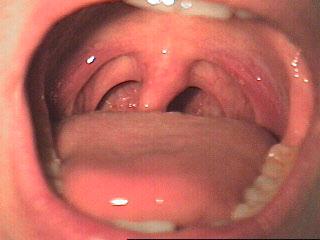

Brush to keep your teeth and friends

Silver fillings tend to be used in posterior teeth because they are stronger material, while composite is for anterior teeth (esthetics)

How is this relatable to dentistry? If you're shade matching a tooth, you would rather have a female asses the shade match for accuracy.